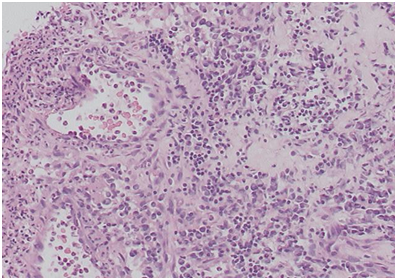

After 5-7days, his local sinonasal symptoms improved but he was as sick as before. Besides persistent headache, he started to have progressive cough and remittent fever. He was also having occasional hemoptysis. The pulmonologists were consulted and they changed the antibiotic and advised tuberculin test, sputum analysis and culture for AFB all of which were negative. They also advised chest CT that showed left lower lung lobe cavitation (Figure 2). More biopsies were taken from the nose and sinuses under general anesthesia and the pulmonologists also did fiber-optic bronchoscopy as per prior arrangement under the same anesthesia, and it was seen that the tracheobronchial tree was congested. However, they did not take any biopsy. There was strong suspicion of pulmonary tuberculosis and anti-tuberculosis therapy was commenced. The biopsy from the nose and sinuses showed non-caseating granuloma but still there was no specific diagnosis.

Figure 2 Left lung lobe cavitation.